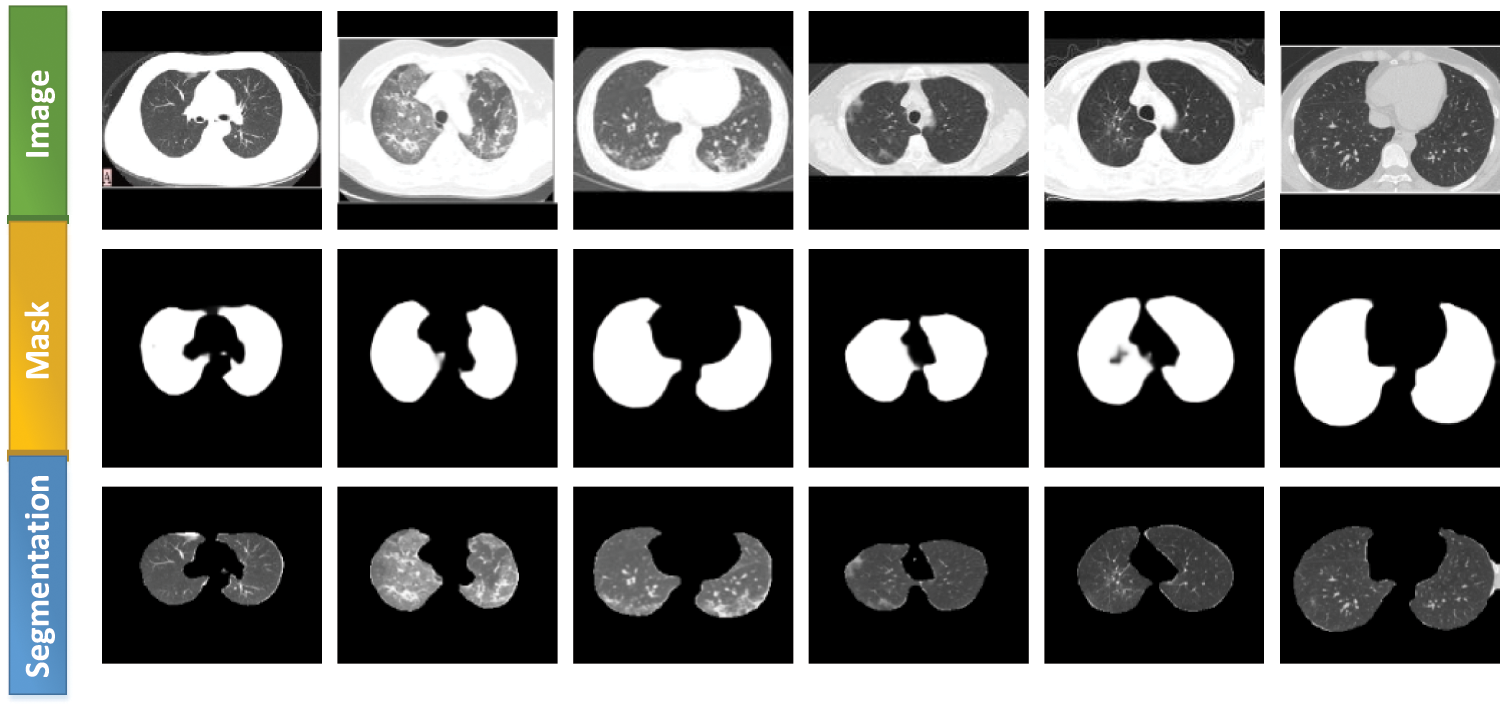

This study used two publicly available datasets: the Data 1 dataset [24] for classification and the Data 2 dataset for data preprocessing. Both datasets had CT images. Data 1 had two categories: COVID-19 (349 images) and non-COVID (397 images). This dataset had image-level labeling, no pixel-level labeling of lesions, and no lung-area labeling. The Data 2 (COVID-19 CT segmentation [25]) was labeled for both lung and focal regions. In this study, we mainly trained the segmentation network using its lung-region-labeled data based on a weakly supervised learning strategy, which made the network recognize the lung region and obtain the learning model. This strategy was used to segment the lung region of Data 1 images. The data preprocessing is shown in Fig. 1. A new set of preprocessed data was finally obtained, named Data1_P.

Figure 1: Data preprocessing using weakly supervised learning

Inf-Net [30] was a segmentation network proposed by Fan et al. This network performed better than all five currently popular segmentation networks: U-Net [31], Attention-UNet [32], Gated-UNet [33], Dense-UNet [34], and U-Net++ [35]. We used lung-region data from Data 2 to train the Inf-Net network, with 80% as the training set and 20% as the test set. The aim was to let the network learn the lung-region features, obtain the segmentation model, and subsequently segment Data 1. Performance evaluation was conducted using six different metrics:

Figure 5: Lung segmentation generated using the Inf-Net network